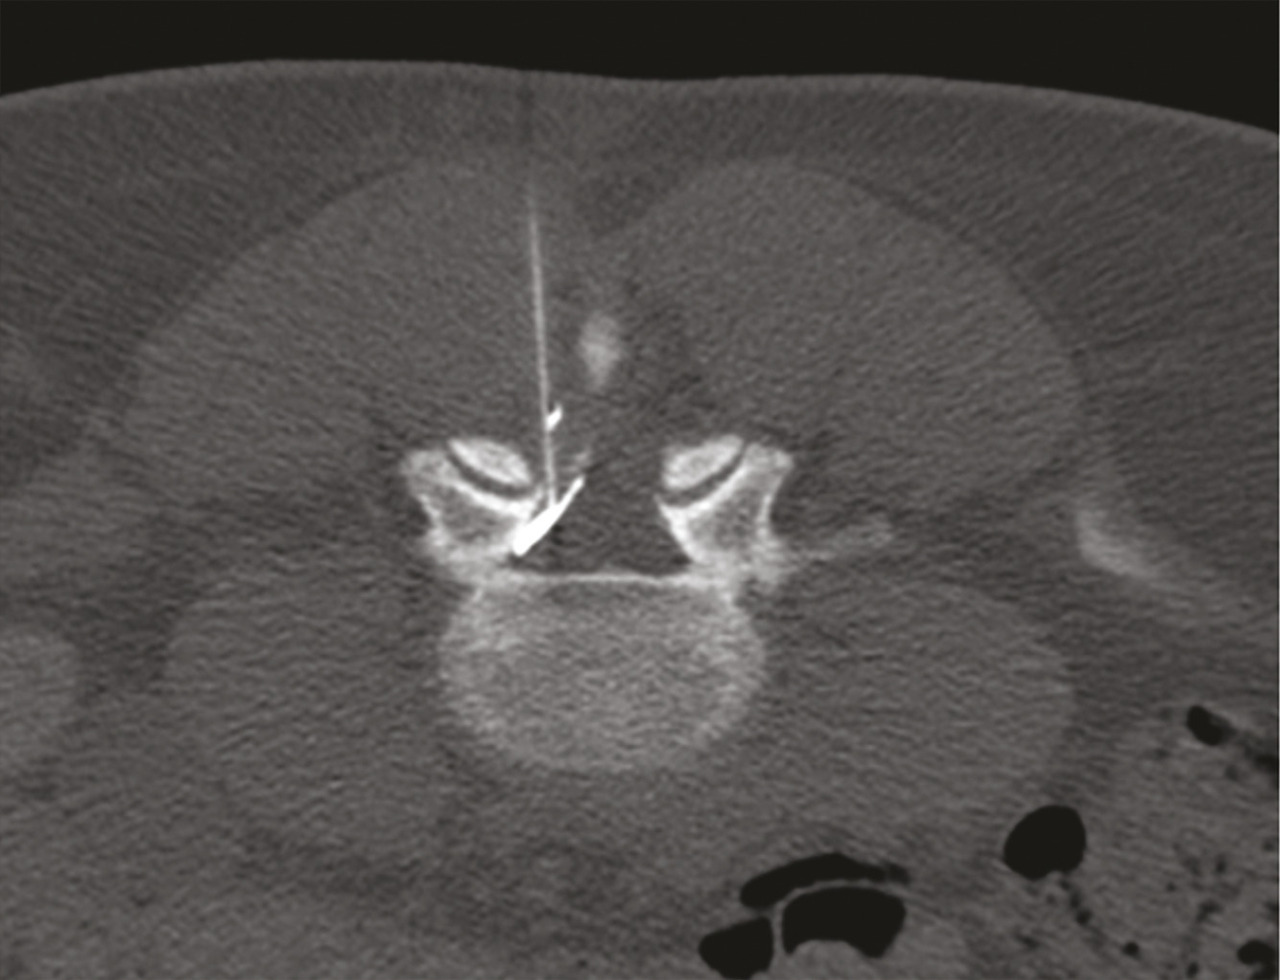

Pour atteindre l’espace épidural, on peut utiliser les voies interépineuse, interlamaire (fig. 1 et 2) ou transforaminale.3, 4 Il existe en outre, à l’étage lombaire, une voie caudale par le ­hiatus sacro-coccygien, mais qui ­nécessite d’injecter au moins 20 mL pour atteindre les racines L4 et L5.5 Tous ces abords se font sous guidage fluoroscopique ou tomodensitométrique, avec injection préalable de produit de contraste, pour vérifier la bonne position de l’aiguille.

L’objectif d’une cimentoplastie ­percutanée (vertébroplastie et kyphoplastie à ballonnets) est double : antalgie et lutte contre la cyphose et le déséquilibre rachidiens. La vertébroplastie percutanée (fig. 5) consiste à injecter par voie transpédiculaire, dans le corps vertébral fracturé, un ciment acrylique (polyméthylmétacrylate) qui est de même nature que celui que l’on utilise pour sceller les prothèses ­articulaires, et dont la tolérance ­biologique est bien établie. Dans la cyphoplastie (ou kyphoplastie) à ­ballonnets (fig. 7), l’injection est précédée d’une tentative de réexpansion du corps vertébral fracturé, grâce à des ballonnets gonflables afin de regagner une partie de la hauteur perdue et de réduire la cyphose.